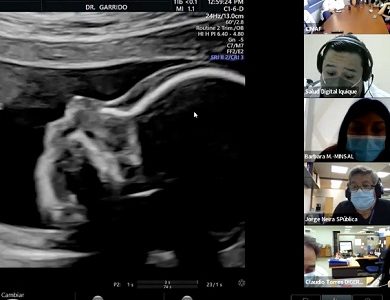

En el Hospital de Iquique realizan examen piloto para detectar Anomalías Congénitas Mayores mediante Telemedicina

Un hito en la medicina regional se llevó a cabo este lunes 13 de diciembre en el policlínico de Alto Riesgo Obstétrico del Hospital Dr. Ernesto Torres Galdames de Iquique, gracias a la estrategia piloto Pichipu -que en mapudungún significa próximo o cercano a- y cuyo objetivo es poner a disposición de la Red Pública de Salud un sistema que permita, a través de Telemedicina Sincrónica, apoyar el diagnóstico en Anomalías Congénitas Mayores (ACM) de manera integrada e interdisciplinaria.

“Es un tremendo hito el tener contacto con la experiencia de médicos que hacen diagnóstico prenatal de alto nivel, y además contar con recomendaciones en el momento. Ojalá que en adelante podamos manejarlo así regularmente porque nos ayudará muchísimo a disminuir tiempos de respuesta y traslados de nuestras pacientes”, sostuvo el médico del servicio de Ginecología y del policlínico de Alto Riesgo Obstétrico del hospital de Iquique, Miguel Estévez.

En tanto que Bárbara Morales, Encargada del Proyecto ACM de la Unidad Hospital Digital del Departamento de Salud Digital, informó que desde octubre de este año trabajaron en proveer los recursos tecnológicos y realizar las pruebas técnicas para lograr esta conexión. “La implementación de esta estrategia se llevará a cabo en cascada. Buscamos proveer y facilitar el acceso a prestaciones de atención especializadas oportunas y de calidad que contribuyan, como en este caso en Iquique, a optimizar los mapas de la red de salud para la resolutividad del diagnóstico de anomalías congénitas mayores” destacó la profesional.